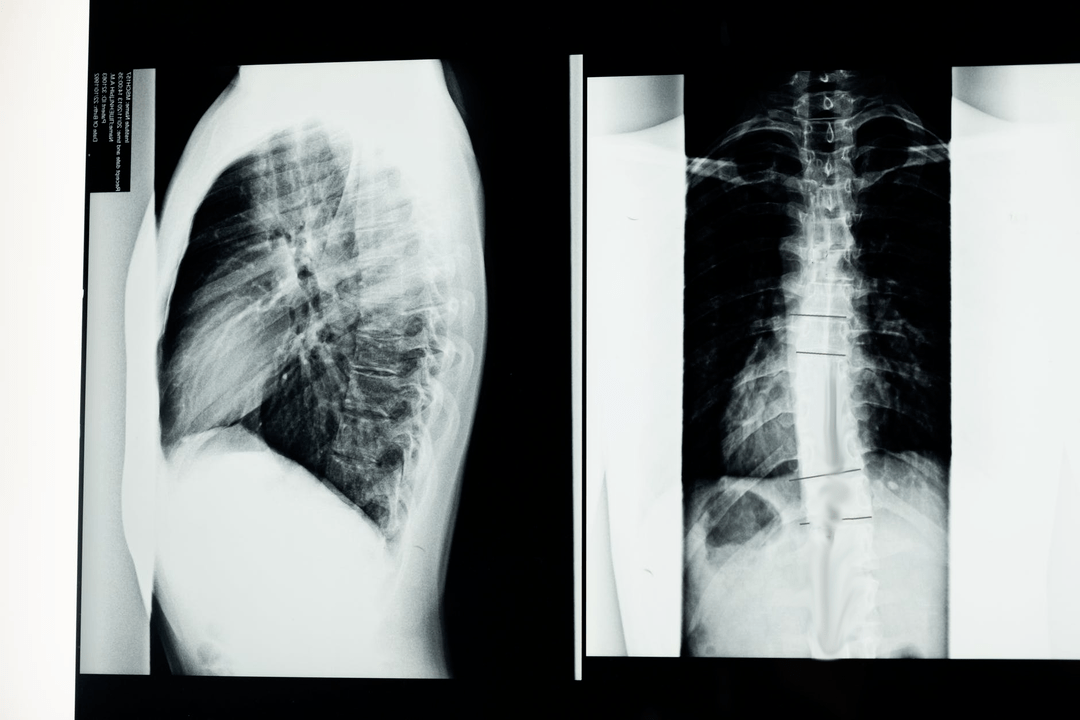

Antes de comezar os estudos diagnósticos, o neurólogo toma a historia clínica do paciente e examina coidadosamente as súas queixas. A osteocondrose ten síntomas comúns a algunhas outras enfermidades, polo que é importante poder distinguir patoloxías. Os estudos de raios X axudan a confirmar o diagnóstico de osteocondrose: radiografía, mielografía e tomografía computarizada.

Unha radiografía de enquisa permítelle tomar unha radiografía da columna vertebral ou unha sección dela. Isto permítelle ao médico determinar a localización afectada pola enfermidade. Para aclarar, explicaremos como se pode determinar a osteocondrose mediante unha radiografía: a imaxe mostra un estreitamento do disco intervertebral, a presenza de crecementos óseos (osteofitos) ou un cambio na forma do segmento espinal.